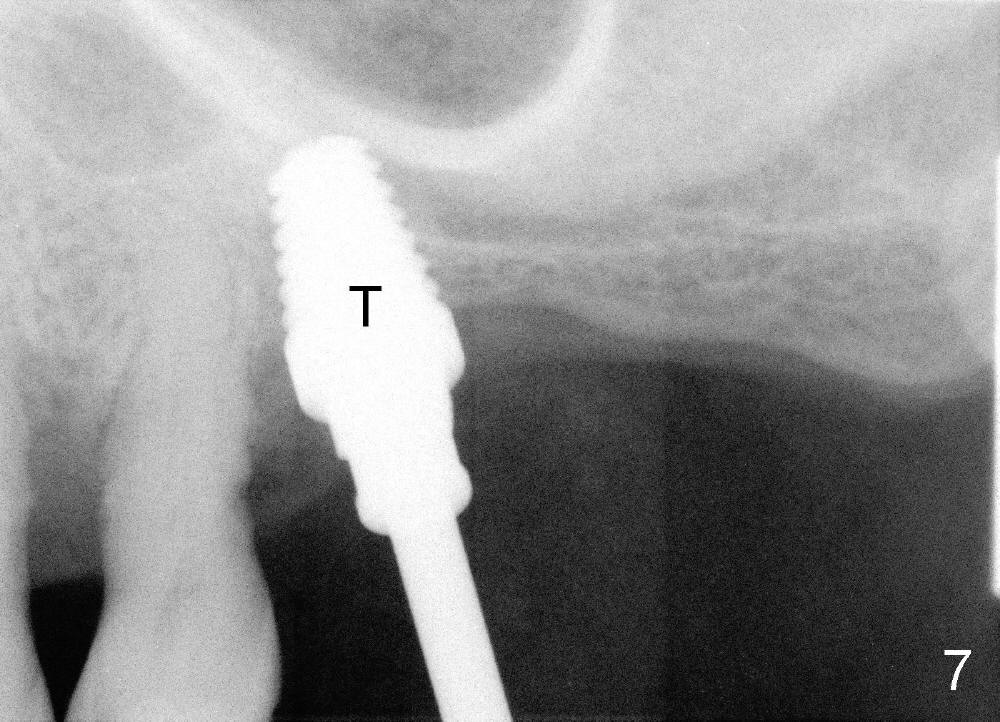

Mr. Wu (54 years old) is also scared of dentistry. He postpones implants for several years. One day he decides to get implant treatment. Easy placement is tried at the sites of #21 and then #7 (Fig.2). He is doing fine postop on both these occasions. Attention is turned to the site of #14 with 2.85 mm bone in height distally (Fig.5 CT sagittal section). The white area represents the crown at the site of #14 (CT scan stent). The coronal section also shows limited bone height (~3 mm) (Fig.6). A 6x11 mm tapered implant is planned to get as large as implant/bone surface area, particularly the mesial aspect (Fig.5,6). Tatum bone expansion technique is used to created osteotomy (#15 blade, BS 4-6 mm, BB 4-10 mm at the depth ~8 mm, RT 2-5 mm at 11 mm, no drill). A 6x11 mm tapered tap is applied (Fig.7 T). It appears that the tap tilts mesially. Adjustment of trajectory is made with RP, RB 4-5 mm at 11 mm and 7x11 mm tapered tap (with resistance). The corresponding implant is placed with >60 Ncm (Fig.8; distal bone quite narrow (between arrowheads). The patient is doing great a month postop with no sign of infection or mobility.